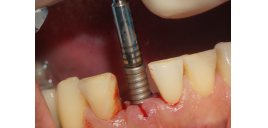

Após os três meses, foi realizada a abertura do implante e foi instalado um cicatrizador, que permaneceu no local por dez minutos para manter os tecidos afastados.

Após esse período, foi selecionado o pilar, e um Pilar Ideale reto de 3.3 X 4.0 X 1.5 mm foi instalado e torqueado a 20 Ncm (Figuras 13 e 14).